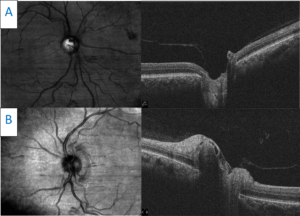

A 51-year-old African American woman presented complaining of painful, sudden vision loss in her right eye approximately 1 week earlier. The pain was noted upon eye movement in all gazes. She stated that her vision was improving since the initial onset of vision loss. Medical history was unremarkable with no known allergies. Entering visual acuity was 20/20- in the right eye and 20/20 in the left. Trace RAPD was observed in the right eye with corresponding 10% dyschromatopsia as measured by red cap desaturation. Extraocular muscle motility was full in both eyes. Confrontation visual field test results were normal in each eye. External ocular exam and slit lamp exam were unremarkable, and IOP measured 14 mmHg in each eye with Goldmann applanation tonometry. Dilated fundus examination revealed an essentially normal appearance of both optic nerves with a cup to disc ratio of 0.45/0.45 in the right eye and 0.35/0.35 in the left eye. OCT RNFL scans revealed one clock hour of borderline thinning inferior-temporal in the right eye and one clock hour of severe thinning inferior-temporal in the left eye. Ganglion cell complex (GCC) analysis showed generalized 360-degree thinning in the right eye with mild inferior-temporal thinning in the left eye (Figure 5). Retrobulbar ON was suspected, and MRI of the brain with and without contrast was performed and found to be essentially normal. Orbital imaging was not obtained. The patient was diagnosed with idiopathic retrobulbar ON and asked to return for follow-up in 3 to 4 months.

Figure 5. Retinal nerve fiber layer scans of both optic nerves showing one clock hour of borderline inferior-temporal thinning in the right eye and one clock hour of severe inferior-temporal thinning in the left eye (A). Ganglion cell complex analysis showing generalized 360-degree thinning in the right eye with mild inferior-temporal thinning in the left eye (B). Click to enlarge

The patient was lost to follow-up but presented again 7 years later complaining of similar painful vision loss, this time in the left eye, for 1 to 2 weeks. Her entering visual acuity was 20/20 OD and 20/60 OS with a 1+ RAPD in the left eye. Entrance testing was otherwise unremarkable. Slit lamp examination was also unremarkable. IOP measured 19 mmHg in the right eye and 18 mmHg in the left eye. Dilated fundus examination revealed generalized optic disc pallor in the right eye. The pallor corresponded to the patient’s history of ON. Examination of the left eye revealed an edematous and hyperemic optic nerve. Cup to disc ratios were stable compared with previous exams. OCT raster scans showed a flat optic nerve in the right eye and nasal elevation and edema of the left optic nerve (Figure 6). Optic nerve head OCT of the right eye showed advanced, generalized thinning of both the GCC and RNFL (Figure 7). This correlated with the patient’s history of ON and her optic nerve presentation (pallor). Optic nerve head OCT scanning of the left eye revealed significant RNFL thickening combined with an inferior-temporal zone of GCC thinning (Figure 7). A recurrence of ON was suspected and repeat MRI of the brain and orbits was performed with and without contrast. The results were essentially normal with patchy, longitudinal enhancement of the left intraorbital segment of the optic nerve (Figure 8). AQP4-IgG and myelin oligodendrocyte glycoprotein (MOG) antibody testing was performed and showed positive anti-MOG titers. A diagnosis of MOGAD ON was established and the patient was treated with pulsed intravenous methylprednisolone followed by an oral prednisone taper. Follow-up visits showed rapid improvement of vision to 20/25 in the left eye in the presence of resultant disc pallor. No RAPD was noted. Repeat OCT showed stable findings of advanced and generalized thinning of both the GCC and RNFL in the right eye. OCT of the left eye showed advanced and generalized thinning of both the GCC and RNFL, which corresponded to the new disc pallor (Figure 9). In the next 2 years, the patient experienced several episodes of ON involving both the right and left eye. With each relapse, she reported rapid vision improvement following treatment with intravenous steroids. She was subsequently placed on maintenance therapy with oral MMF and her condition has remained stable with no further recurrences.

![]() Figure 6. Horizontal raster scans taken through the center point of both optic nerves. A: The right optic disc is flat with significant cupping. B: The left optic disc scan shows moderate elevation and edema. Click to enlarge |

![]() Figure 7. A: Retinal nerve fiber layer (RNFL) analysis of both eyes. In the right eye, advanced RNFL thinning, sparing the nasal portion of the nerve, is seen. Compared with the previous scans (Figure 5), progression is illustrated by a lower average thickness and deeper and larger amounts of thinning on the deviation map. Analysis of the left eye shows acute RNFL thickening, greater superiorly than inferiorly, which was not noted in the previous scans (Figure 5). B: Ganglion cell analysis of both eyes. Advanced ganglion cell complex (GCC) thinning is present in the right eye. This corresponds with the patient’s previous bout of optic neuritis. Compared with previous scans (Figure 5), progressive GCC thinning is illustrated in the right eye by a lower average GCC thickness. Inferior-temporal GCC thinning is noted in the left eye. The scan is relatively stable when compared with the previous scan (Figure 5). |